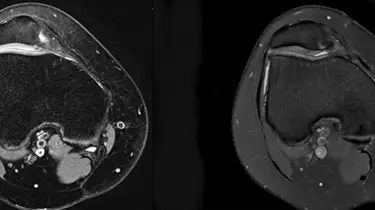

Ortopædkirurgi Lars Blønd har for nyligt udviklet en ny og vellykket operationsteknik til behandling af Artroscopisk Trokleoplastik, der udføres med en kikkertoperation.